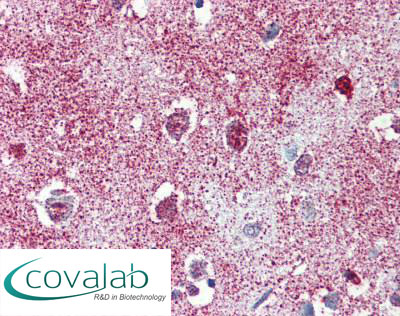

Anti-TAOK1 antibody IHC staining of formalin-fixed, paraffin-embedded human cortex after heat-induced antigen retrieval.

Anti-TAOK1 antibody IHC staining of formalin-fixed, paraffin-embedded human cortex after heat-induced antigen retrieval.